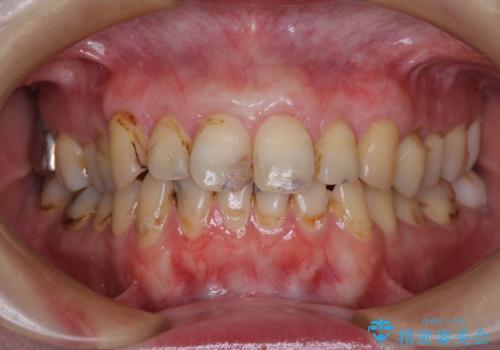

前歯は着色や虫歯治療の跡が目立っている状態で、オールセラミッククラウンによる審美治療を希望されていました。

歯肉が非常に菲薄であり、オールセラミッククラウンを装着後の近い将来歯肉退縮によりセラミックの境目が見えてくることが懸念されました。

犬歯を中心に、露出量の多かった歯は十分に被覆することができました。

また、歯根のシルエットが見えた術前の状態と比較して、術後は歯肉が非常に厚くなっている状態となりました。